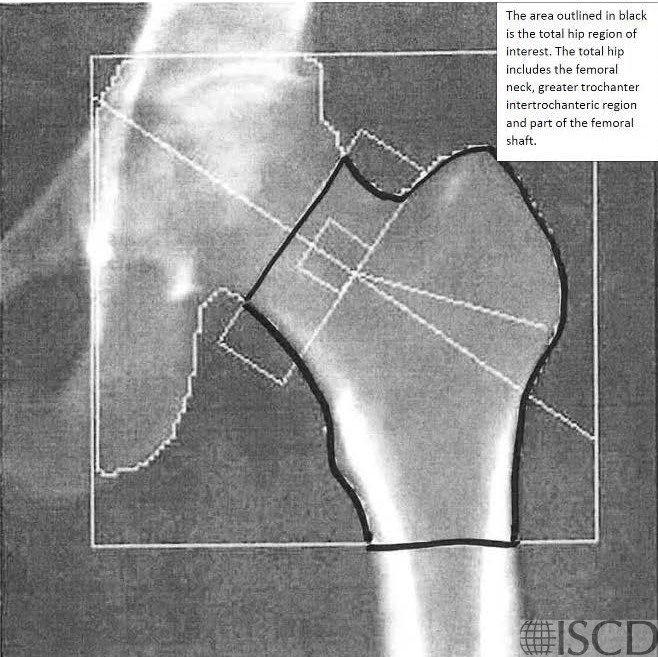

The image shows the total hip region of interest.

This image shows the femoral neck box and the femoral neck region of interest.

The hip that is scanned is internally rotated using a hip positioner. The hip is internally rotated because that makes the femoral neck parallel to the scanner bed. The default width of the femoral neck box is 15 pixels. The analysis is stepped through and a line is placed on various landmarks (i.e. head of the femur, greater trochanter and bottom of the lesser trochanter) and this positions the global region of interest box of the hip scan. It is the bottom of the hip global region of interest that is most important related to total hip results on a Hologic scan. The bottom of the global region of interest should be 10 pixels below the bottom of the lesser trochanter. The lesser trochanter may be better defined by altering the contrast on the scan. If the femoral neck overlaps the ischium, the edge detection may be altered to paint out that portion of the ischium.